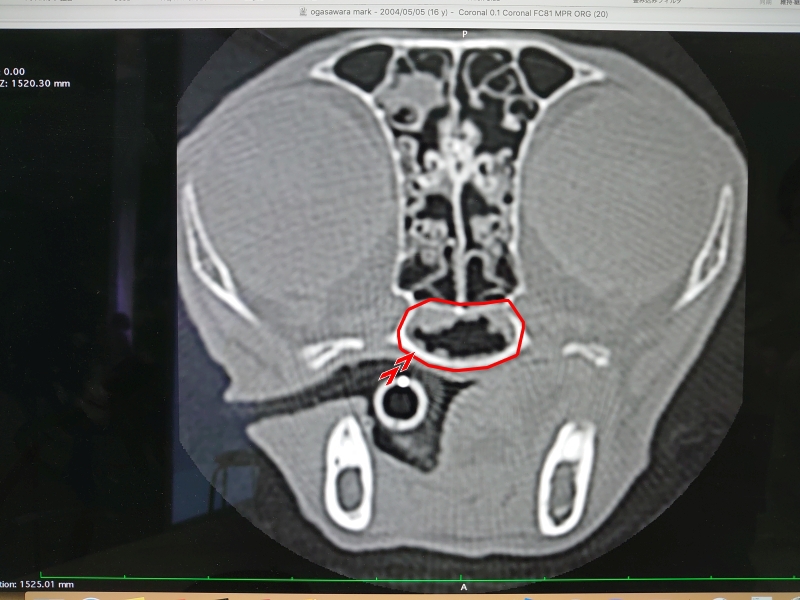

先生からCTと内視鏡の映像を見せてもらった

鼻咽頭内にぼこぼこしたものがへばりついてる..

確かに先日見せてもらったワンちゃんの狭窄とは異なり、空洞は広いようだけど何かがへばりついてる..

先生が言っていた「ぼこぼこしたもの」は、この白いぼこぼこのことだった

鼻咽頭内は膿とか血液とか鼻汁とかはなく、ただぼこぼこしたものが覆い尽くしている..

先生の所見では今のところこれが炎症によるものなのか、リンパ腫なのかは判断できないとのこと..